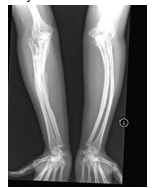

• Fractures

•Multiple fractures are more common after physical abuse than after non-abusive traumatic injury

•A child with rib fractures has a 7 in 10 chance of having been abused

•A child with a femoral fracture has a 1 in 3-4 chance of having been abused

•Femoral fractures resulting from abuse are more commonly seen in  children who are not yet walking